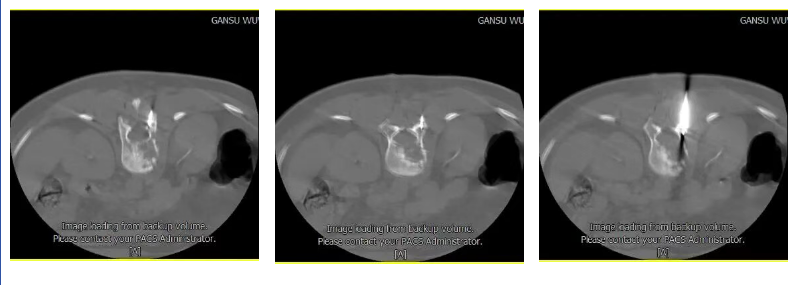

b:避依据测量进针深度,植入穿刺针,经过椎弓根或者椎弓根外侧缘进行穿刺,多次扫描确定进针的方向和深度,避免进入椎管;随时调整进针方向;

c:穿刺针经过椎弓根,准确进入椎体病变区域;

d:应用推杆少量多次注入骨水泥,观察病变区域骨水泥的填塞状况;